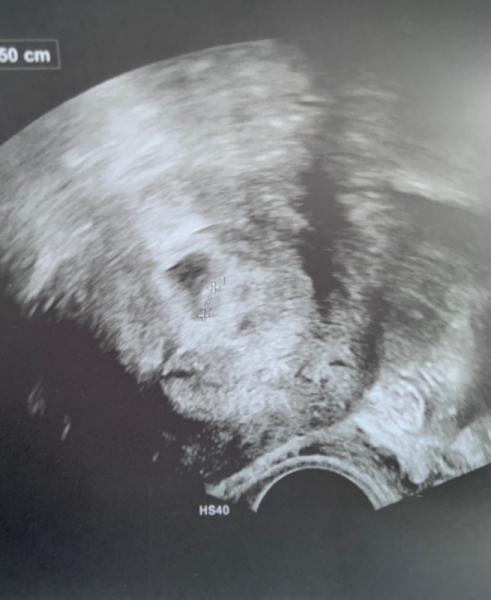

Danke an alle.. leider hat man noch nicht so viel gesehen. Naja es ist auf jeden Fall was drin, das beruhigt mich schon sehr aber die Ärztin war unsicher und will daher am Montag nochmal nachschauen. Hauptsache es ist ein Dottersack und eine Anlage sichtbar... oder ? Bin hin und hergerissen was ich davon halten soll. Sie wird nun HCG messen.

Bild zu